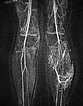

Die koronare T1-gewichtete native MRT zeigt eine intramuskuläre, gefäßreiche Läsion (isointens zur Muskulatur) mit deutlich zwischengelagertem hyperintensem Fettgewebe, mehr als bei einer normalen venösen Malformation üblich.

In der kontrastmittelunterstützen MR-Angiographie (MIP) zeigt sich ein komplettes Enhancement der venösen Malformationskomponente in der linken Wade mit Kontrastmittelpooling.

Die Kontroll-MR-Angiographie zeigt eine deutliche Befundbesserung. Die dysplastischen, erweiterten Kanäle der venösen Malformation sind zu einem guten Teil verschlossen.

In der koronaren nativen T1-gewichteten Kontroll-MRT sind die Gefäßanteile der Läsion deutlich weniger abgrenzbar. Es bleibt jedoch deutlich zusätzliches Gewebe bestehen („Salz-und-Pfeffer-Muster“), zum Teil hyperintenses Fettgewebe, zum Teil hypointenses Bindegewebe. Dies ist typisch für eine Fibro-adipose Vascular Anomaly (FAVA).